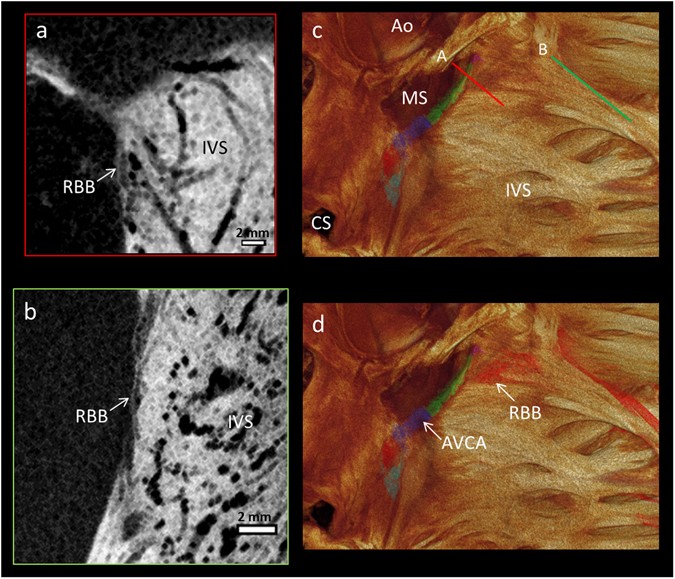

Figure 4

Segmentation of the right bundle branch. The high resolution (73 × 73 × 73 µm3) micro-CT data from the whole human heart, showing the 3D extent and position of the segmented right bundle branch (red in panel d) on the lateral aspect of the interventricular septum (c,d), as viewed from within the right ventricular cavity. Illustrative long-axis micro-CT sections showing the proximal (a) and distal (b) aspects of the right bundle branch. From the view in (d) a part of the so-called dead-end tract at the anterior/rostral extent of the atrioventricular conduction axis can be identified (purple). The position of the cross-sections (a,b) are shown in the 3D volume rendering in (c). Ao- Aortic root, AVCA- atrioventricular conduction axis, CS- coronary sinus, IVS- interventricular septum, MS- membranous septum, RBB- right bundle branch.